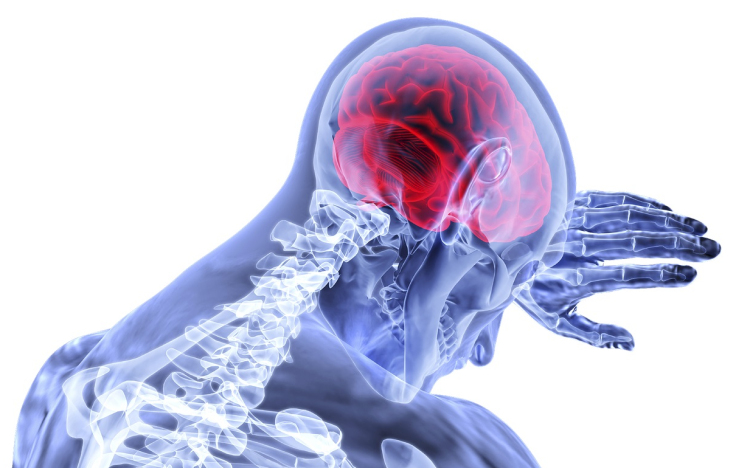

Folytatódhat az agy működését és betegségeit vizsgáló kutatás a pécsi egyetemen

A következő négy évben is folytatódhat a Pécsi Tudományegyetemen (PTE) az a kutatómunka, amelyet az elmúlt években huszonöt kutatócsoport száz szakembere végzett az agy működését és betegségeit érintően

A PTE közleménye szerint a Nemzeti Kutatási, Fejlesztési és Innovációs Hivatal Tématerületi Kiválósági Programja 1,49 milliárd forintos keretéből tudományokon átívelve folytatódhat az emberi agy működését, betegségeit érintő kutatások.

Dóczi Tamást, a PTE idegsebész professzorát, a projekt vezetőjét idézve jelezték: az agy működésének megértése és betegségeinek gyógyítása korunk legnagyobb tudományos kihívásai közé tartozik, a huszonöt kutatócsoport az új programban éppen ezért a korábbi kutatások teljeskörű megvalósítására, illetve új kutatási célpontok kijelölésére törekszik.

A kutatók - egyebek mellett - szeretnék a korábbiaknál jobban megismerni és megérteni az agy fejlődését, öregedését, vizsgálják az érzékszervektől érkező, illetve az emlékezettel kapcsolatos információk agyi feldolgozását, továbbá a szerv rendellenességei, betegségei kezelését segítő terápiák kidolgozását támogatnák.

A kutatásokban a PTE idegtudományi centruma, az orvosi, a természettudományi és a gyógyszerésztudományi kar, a klinika és a Szentágothai János kutatóközpont munkatársai vesznek részt.